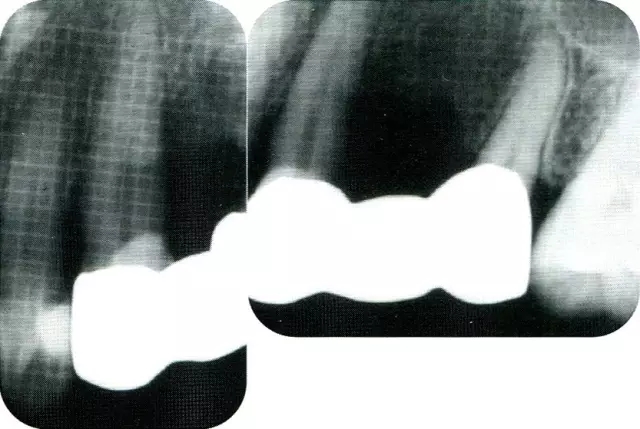

640.webp (2).jpg

▲圖7-3  將posterior interproximal類型的非吸收性覆膜修整后進行垂直懸吊縫合做固定。垂直懸吊縫合后,確定覆膜是否會動搖,再將齦瓣與之緊密縫合。